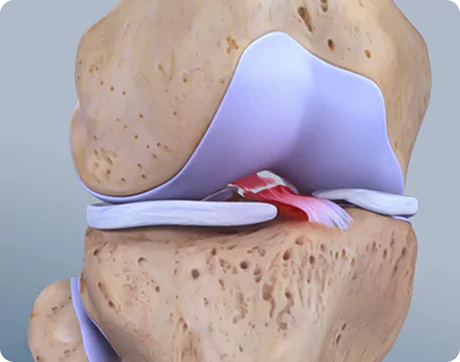

What Is Spine Surgery?

Spine surgery is a medical intervention aimed at treating conditions that affect the spinal column and spinal nerves. It becomes necessary when conservative treatments such as physiotherapy, medications, or injections fail to relieve persistent symptoms like chronic back pain, sciatica, or nerve compression.

The spine is a complex structure composed of vertebrae, discs, nerves, and ligaments. Problems in any of these areas can lead to severe pain, restricted movement, or neurological symptoms. Spine surgery helps to correct structural abnormalities, relieve pressure on spinal nerves, stabilise the spine, and restore function.